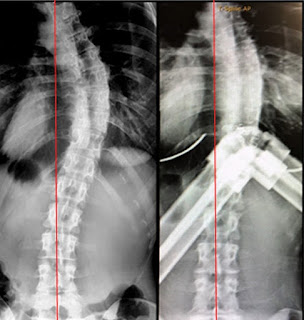

Here is an x-ray comparison to show how my spine reacts with the Torso Trainer.

| Left: Pic of x-ray without torso trainer, Right: Pic of x-ray wearing torso trainer |